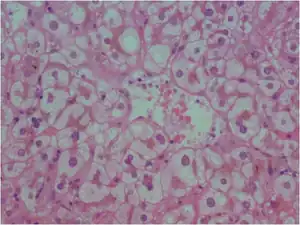

| Liver biopsy in acute fatty liver of pregnancy showing microvesicular fatty infiltration of the hepatocytes | |

If a liver biopsy is needed for diagnosis of the condition, the mother should be appropriately stabilized and treated to reduce bleeding related complications. The diagnosis can be made by a frozen-section (as opposed to a specimen in formalin) that is stained with the Oil red O stain, that shows microvesicular steatosis (or small collections of fat within the liver cells). The microvesicular steatosis usually spares zone one of the liver, which is the area closest to the hepatic artery. On the regular trichrome stain, the liver cell cytoplasm shows a foamy appearance due to the prominence of fat. Necrosis is rarely seen. The diagnosis can be enhanced by electron microscopy which can be used to confirm the presence of microvesicular steatosis, and specifically the presence of megamitochondria and paracrystalline inclusions.[21][22] Liver diseases with similar appearances include Reye's syndrome, drug-induced hepatitis from agents with mitochondrial toxicity, including nucleoside reverse transcriptase inhibitors used to treat HIV,[23] and a rare condition known as Jamaican vomiting sickness which is caused by the eating of the unripened Ackee fruit.[24]